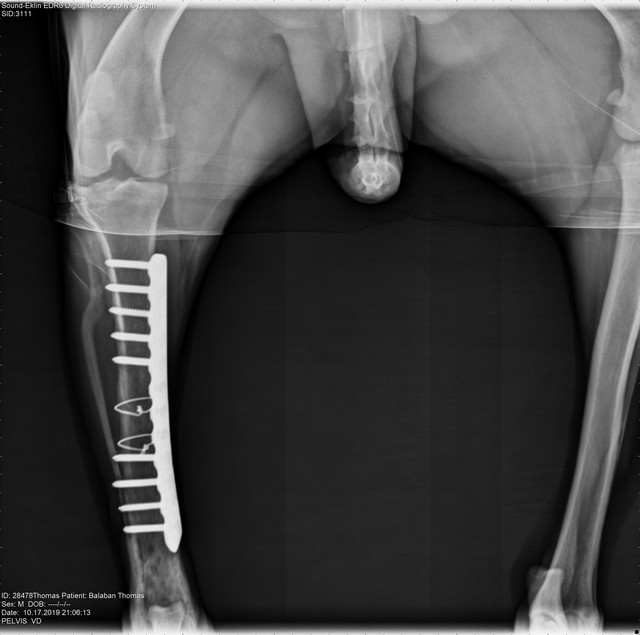

Наиболее распространенным способом лечения данной злокачественной опухоли является ампутация пораженной конечности с последующей химиотерапией. Иногда проводятся операции с сохранением конечности, если опухолью поражено не более 50% кости и она не распространилась на окружающие мышцы. При таком методе пораженная кость удаляется хирургическим путем и заменяется костным трансплантатом.

Протезированием лучевой кости у собаки после удаления саркомы.

| Рис. 4. Остеогенная саркома. | Рис. 5. После постановки имплантата. | Рис. 6. Замещение удаленного участка кости акриловым полимером с использованием пластины. | |

После удаления части кости на ее место устанавливается индивидуально подобранный имплантат (специальная титановая пластина с повышенной степенью прочности) в сочетании с костным цементом, который заполняет недостающую часть кости (Рис. 11). Именно имплантаты в последующем и будут являться опорой для кости. Подбор имплантов очень важен так как они должны обладать достаточной прочностью и поэтому наши врачи одни из первых в России стали использовать современные LCP имплантаты (блокируемые пластины и блокируемые гвозди) (Рис.

12, 13, 14).